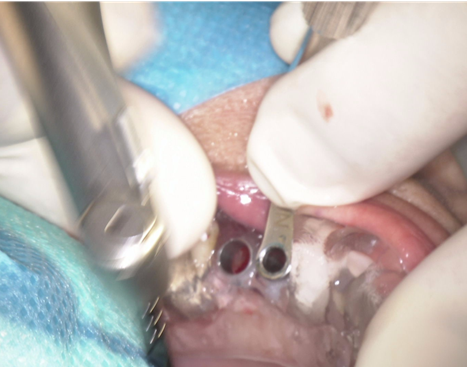

③ガイデッドサージェリーにてインプラント埋入しました。

④計画通りの埋入が出来ました。

レントゲン写真でも理想的な位置

に埋入できました。